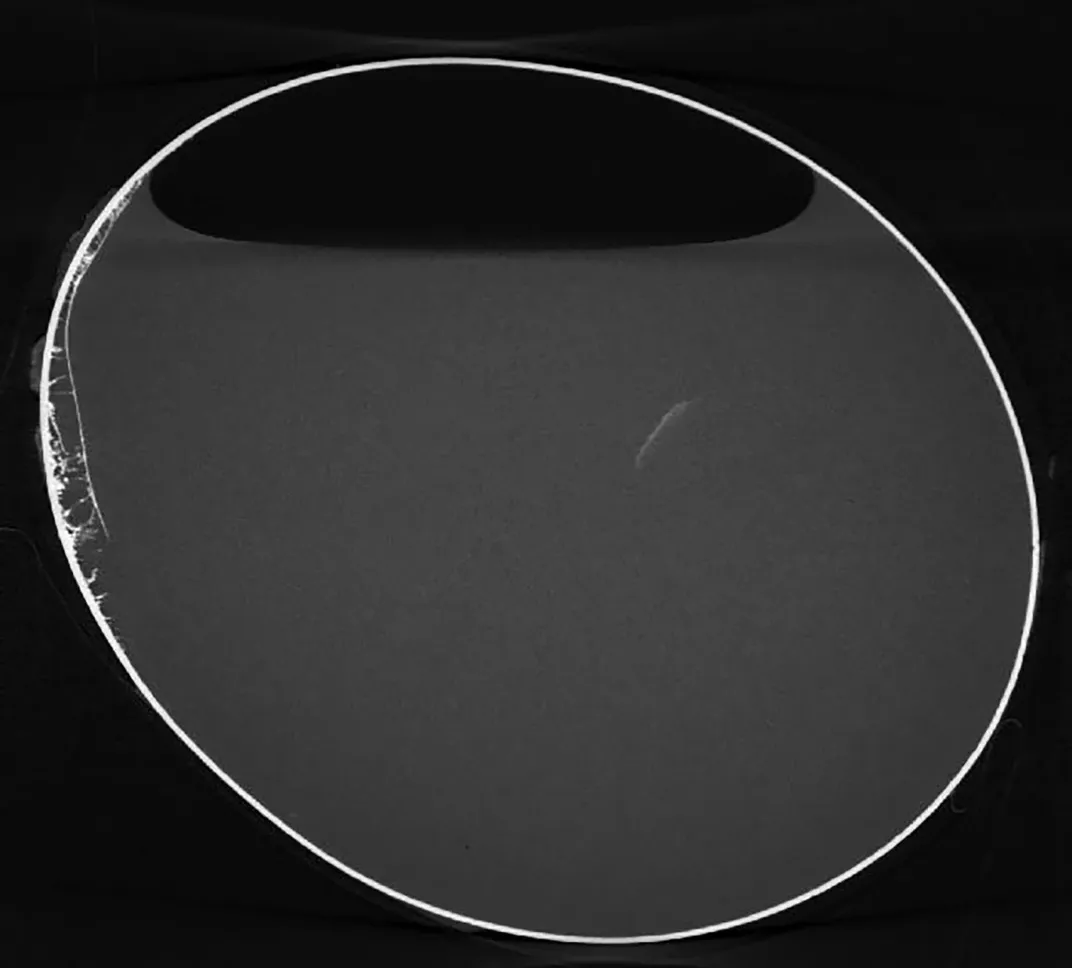

Cuộc thảo luận đã diễn ra để quyết định cách trưng bày và bảo quản quả trứng kỳ lạ này, và sau khi quét quả trứng, phát hiện rằng nó vẫn chứa chất lỏng và bọt khí. Điều này khiến các nhà khảo cổ kinh ngạc vì đây có thể là quả trứng cổ nhất trên thế giới.